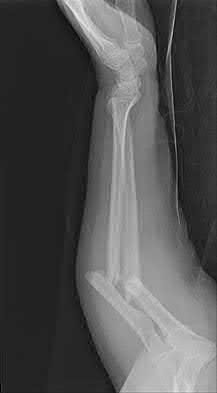

A 22-year-old male cyclist was struck by a car. He complains of right knee pain and swelling, as well as reduced sensation and weakness in his right foot. His leg compartments are soft and not tender. Distal pulses in the extremity are palpable. Radiographs of the knee, as shown in Figures A and B, were taken after a closed reduction maneuver was performed. What would be the next best step in management of this patient?

This patient presents with a Schatzker IV tibia plateau fracture with lower extremity neurologic deficits. The next best step would be to investigate for an acute vascular injury with ankle-brachial index measurements.

Fracture-dislocations of the knee must be suspected with all Schatzker type IV injuries as this fracture pattern is usually associated with high energy trauma. Identifying this injury should prompt a thorough assessment of the neurovascular structures across the knee. After closed reduction and emergent immobilization of the knee, ankle brachial indices (ABI) must be immediately performed. If

Knee dislocations are associated with popliteal artery injury in 18-45% of cases and range from intimal tears to complete transection. Amputation rates of 85% have been reported if revascularization is delayed greater than 6 to 8 hours.

Neurologic injury occurs in 15-40% of cases and is most common after posterolateral dislocation. The peroneal nerve is more commonly injured.

Rihn et al. reviewed the acutely dislocated knee. They recommend a vascular consult if pulses are weak, or ABI is compromised. They warn that in arterial injury, pulses, temperature and capillary refill can be normal. If the limb remains ischemic, surgical exploration and revascularization is indicated.

Medina et al. systematically reviewed neurovascular injury after knee dislocation in 862 patients. Vascular injury rate was 18%, and nerve injury rate was 25%. Repair was performed in 80% of vascular injuries, and amputation in 12%. The most vascular injury was seen in KDIIIL injuries (32%) and posterior dislocation (25%).

Figure A is an AP radiograph of a posterior knee dislocation. Figure B is a lateral showing the same injury.